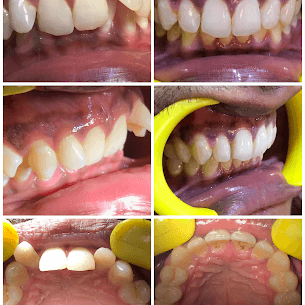

- TREATMENTS:

Crown Restoration

- INFO:

Crown treatment for 16-year-old with broken teeth